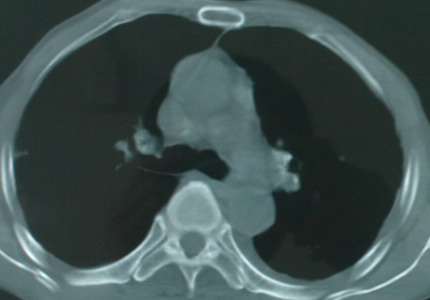

以下是引用医影拾贝在2008-6-3 18:48:00的发言:[br]双上肺弥漫性小结节影,纵隔窗内钙化淋巴结影,考虑血播性tb可能性较大,不除外肺ca可能

以下是引用卜一在2008-6-3 19:33:00的发言:[br]双肺结节,以双上肺分布为多,期间搀杂片状致密影及索条致密影。考虑:继发性肺结核伴血型播散可能性大。不除外肺泡ca的可能!另:椎体退变!

以下是引用panyishengct在2008-6-3 21:09:00的发言:[br]双上肺弥漫性小结节影,纵隔窗内钙化淋巴结影,考虑矽肺或/和tb可能性较大,不除外肺ca可能。腰椎考虑退变。 [br][br]